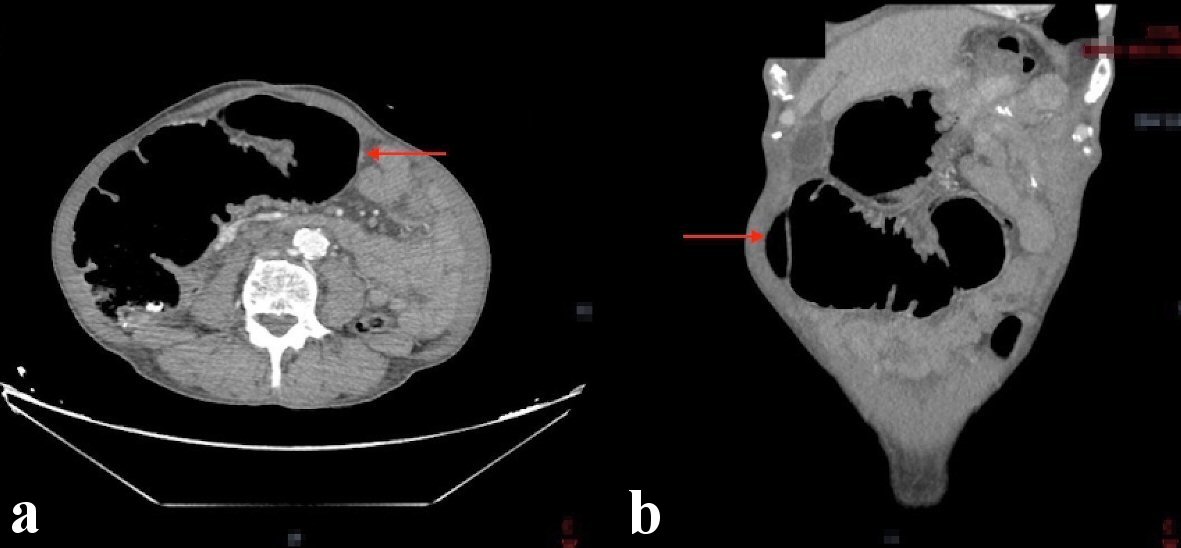

Notable laboratory workup included a complete blood count showed a white blood cell count of 3.8 × 103/µL, hemoglobin of 8.7 g/dL, and a platelet count of 312 × 103/µL. A comprehensive metabolic panel showed a normal creatinine of 1.1 mg/dL, blood urea nitrogen of 21 mg/dL and electrolytes within normal limits. Given the patients symptoms a computed tomography (CT) scan of the abdomen with intravenous contrast was done and showed an apple core mass of the mid-transverse colon measuring approximately 30 × 44 mm. There was also marked dilation of the colon proximal to this, consistent with large bowel obstruction (Fig. 1).

![]() Click for large image | Figure 1. CT abdomen showing a mid-transverse colon mass measuring 30 × 44 mm resulting in proximal colonic obstruction (red arrows). (a) Axial view. (b) Coronal view. CT: computed tomography. |